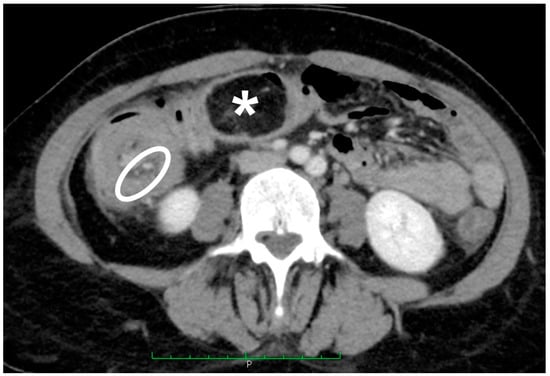

Figure 3.

Axial CT scan of the abdomen in portal/venous phase. Circumferential thickening in ileocolic intussusception caused by the lipoma; note the mesenteric fat and vessels (white oval) and the terminal ileum associated with the intussuscipiens (asterisk).

Given the presence of intussusception, with initial signs of the ischemic suffering of the bowel (Figure 3), immediate surgery was offered.